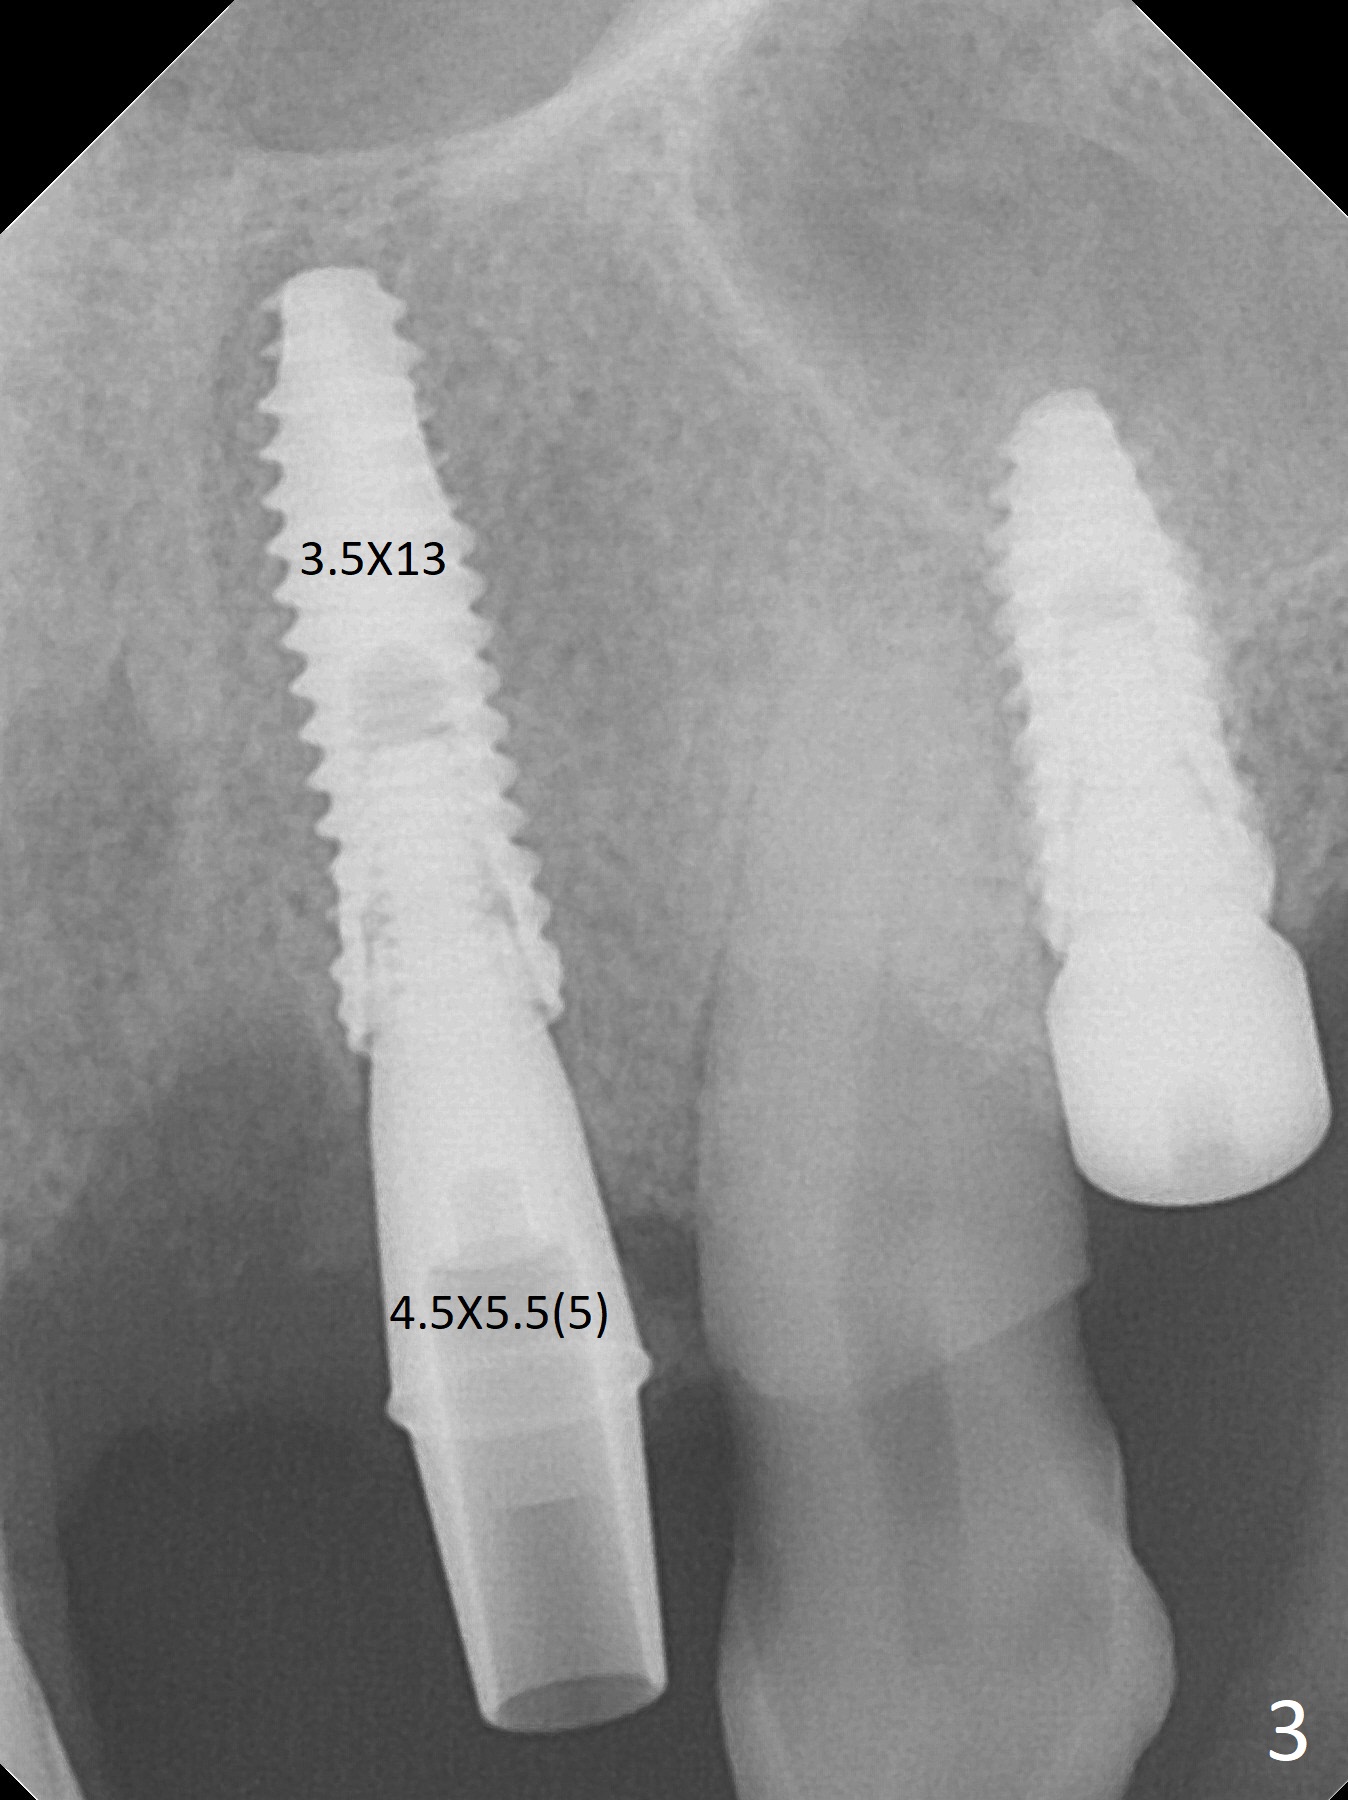

After a 4x10 mm implant is placed with fixture mounting (Fig.2 M) following sinus lift (*) at #12, osteotomy is initiated at #10 (Fig.1 (T: tube of surgical guide)). It appears that the drill (D) has good trajectory (between the Incisive Canal (red dashed line) and the canine root). The final position of the implant at #10 is acceptable (Fig.3). The implant at #12 is placed deeper (Fig.4 (arrow), as compared to Fig.2) because of clinically buccal superficial placement. The most critical challenge is anterior deep bite associated with posterior collapse. Periodontal dressing is applied. When the latter dislodges, there is minimal clearance for a provisional. Periodontal dressing is re-applied. The patient (smoker, partial edentulism with occlusal interference) returns for provisional nearly 1 month postop with chief complaint "something is lost in the back". In fact the healing abutment at #12 is lost with buccal granulation tissue (Fig.5). When a new abutment is seated, there is discomfort. When a healing screw is placed, it cannot be seated completely with two separate trials (Fig.6,7). Should we leave it as it is or open up for complete seating? It appears that the implant is loose. After preparation for clearance at #10, the abutment is retightened. It appears to turn with the underlying implant with discomfort. A 4x5 mm healing abutment is placed to reduce micro-movement. One week later, the infection at #12 dissolves with oral Amoxicillin (Fig.8). Due to limited occlusal clearance and implant tenderness when the abutment abutment is retightened, the cemented abutment is changed to a healing abutment. The implant at #10 seems to be osteointegrated, while the healing screw at #12 remains incomplete seating 3 months postop (Fig.9). The loose healing screw cannot be retightened securely, as there is bone loss around the implant 3 months postop (Fig.10 *). When a 4.5 mm x 15 degree 4 mm cuff angled abutment is placed, the mesiodistal trajectory improves (Fig.11), but there is no occlusal clearance (Fig.12). The latter would form when posterior support is established (Fig.13, either removable appliance (which the patient hates) or fixed one (finance)). Fig.14 shows the unhealed site of #12. Incision confirms the bone loss around the implant, which is removed. Although the sinus floor is absent, there is no membrane perforation. After debridement, allograft mixed with small amount of Osteogen is placed (Fig.15,16 G) and covered with Osteogen plug and 6-month membrane.